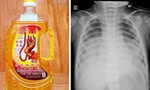

| Hai cháu bé còn lại đang được chăm sóc đặc biệt tại Khoa Nhi |

Trước đó, tối 13/7, 2 cháu Y.L.Đ và Y.M.H (cùng 4 tuổi, trú xã Rờ Kơi, huyện Sa Thầy) đến cấp cứu tại Bệnh viện Đa khoa tỉnh trong tình trạng mệt mỏi, buồn nôn.

Được bác sĩ cấp cứu ngay sau đó, tuy nhiên do uống phải lượng lớn chất tẩy rửa nên bé Đ đã ngưng thở, ngưng tim. Còn bé H đã giảm bớt các triệu chứng ngộ độc, đang được theo dõi, chăm sóc.

Theo các gia đình, cả 3 bé trên đều uống hóa chất rửa xe có màu hồng, mùi thơm vị bạc hà, không có nhãn hiệu vì nhầm lẫn đây là nước ngọt.